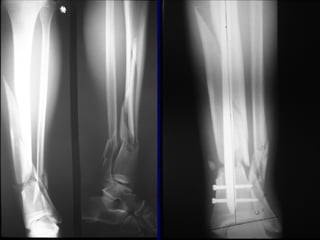

Radiographic Evaluation

• AP and Lat views of entire tib/fib required

from knee to ankle

• Oblique views can be helpful in follow-up

to assess healing

Associated Injuries

• Up to 30% of patients

with tibial fractures have

multiple injuries*

• Fracture of the ipsilateral

fibula common

• Ligamentous injury of

knee common in high

energy tibia fractures

*Browner and Jupiter, Skeletal Trauma, 2nd

Ed